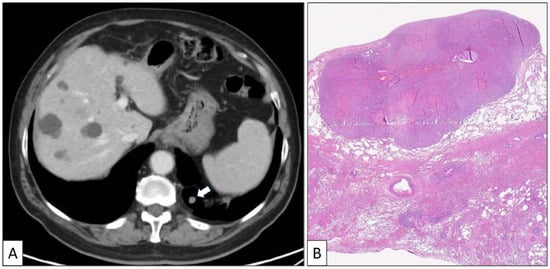

Figure 3.

Histological patterns of sclerosing pneumocytoma, including sclerotic (A) and solid (B) (hematoxylin-eosin, original magnification ×100).

The atypical left lower lung resection showed a tumor with well-defined limits growing into the lung parenchyma close to the pleura (Figure 2B). The tumor displayed a predominantly dense proliferation of cells with sclerotic (Figure 3A), solid (Figure 3B), and hemorrhagic (Figure 3C) areas. At the tumor periphery, no infiltrative borders were seen and necrosis was not detected. A closer view presented a biphasic cellular pattern with stromal-appearing cells together with surface cells (Figure 4A). No atypia or mitosis was seen. Foamy macrophages were occasionally detected.